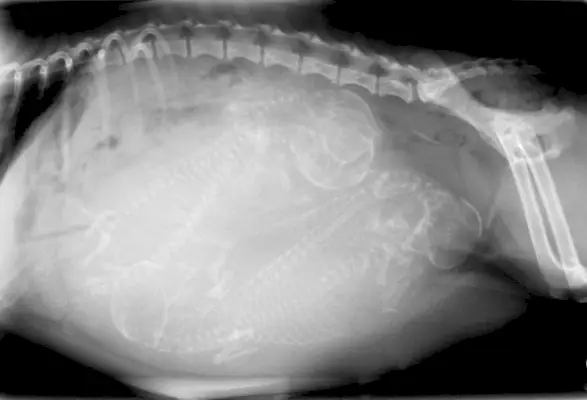

Avhengig av kjæledyrets medisinske problem eller skade, kan røntgenbilder være en en-og-gjort situasjon. Men i noen tilfeller brukes de rutinemessig for å holde et øye med utviklingen av en sykdom eller for å overvåke en vanskelig graviditet. Så nå som du vet viktigheten av røntgenbilder for hunder, la oss se på hvor mye de kan koste.

Andre tilfeller som kan trenge røntgenstråler med jevne mellomrom kan være å overvåke effektiviteten av behandling av et organ, helingsprosessen av en skade, eller å holde øye med et tannproblem, for eksempel tannkjøttsykdom.